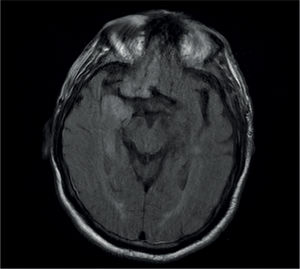

Los síndromes paraneoplásicos son las manifestaciones clínicas de un tumor que no están relacionadas con la invasión directa del tumor primario o de sus metástasis. Se excluyen asimismo las complicaciones cerebrovasculares, infecciosas, metabólicas nutricionales o tóxicas asociadas a las neoplasias y también las derivadas del tratamiento (quirúrgico, radioterapia, quimioterapia o terapias biológicas). Comprenden un grupo heterogéneo de síndromes que pueden afectar a cualquier parte del sistema nervioso central (SNC) o periférico (SNP), unión neuromuscular y músculo, y en ocasiones en el mismo paciente en múltiples áreas. Son poco frecuentes, con una incidencia general en pacientes con cáncer inferior al 1%. La incidencia varía con el tipo de tumor, siendo los más implicados el cáncer de pulmón de células pequeñas (CPCP) con un 3% de incidencia. La presencia de anticuerpos onconeuronales apoya el diagnóstico en un síndrome clínico compatible; sin embargo, solo están presentes en aproximadamente un 50% de los casos, por lo que su ausencia no descarta el diagnóstico. Como ya se ha mencionado anteriormente, el síndrome paraneoplásico se puede producir en pacientes con una neoplasia ya diagnosticada, pero en muchos casos esta no es aparente, por lo que es preciso ante la presencia del síndrome la búsqueda de la neoplasia oculta. Si es posible se debe iniciar el tratamiento lo antes posible, pues los síndromes paraneoplásicos evolucionan en unas semanas, pudiendo producir un daño irreversible e incluso la muerte del paciente.

Paraneoplastic syndromes are clinical manifestations of a tumor that are not related to the direct invasion of the primary tumor or its metastases. Therefore, cerebrovascular, infectious, nutritional metabolic, or toxic complications associated with neoplasms and also treatment-derived complications (surgery, radiotherapy, chemotherapy, or biologic therapies) are excluded. They comprise a heterogeneous group of syndromes that can affect any part of the central nervous system (CNS) or peripheral nervous system (PNS), neuromuscular junction, and muscle and occasionally affect multiple areas in the same patient. They are uncommon, with a general incidence in patients with cancer of less than 1%. Incidence varies according to the type of tumor, with small cell lung cancer (SCLC) being the most commonly involved, with an incidence of 3%. The presence of onconeural antibodies supports the diagnosis of a compatible clinical syndrome. However, they are only present in approximately 50% of cases and therefore its absence does not rule out a diagnosis. As previously stated, paraneoplastic syndrome can occur in patients with an already-diagnosed neoplasm, but it is not apparent in many cases. Therefore, the search for the occult neoplasm is necessary when the syndrome is present. If possible, treatment must be started as soon as possible, given that paraneoplastic syndromes progress in weeks and can cause irreversible damage or even the patient's death.